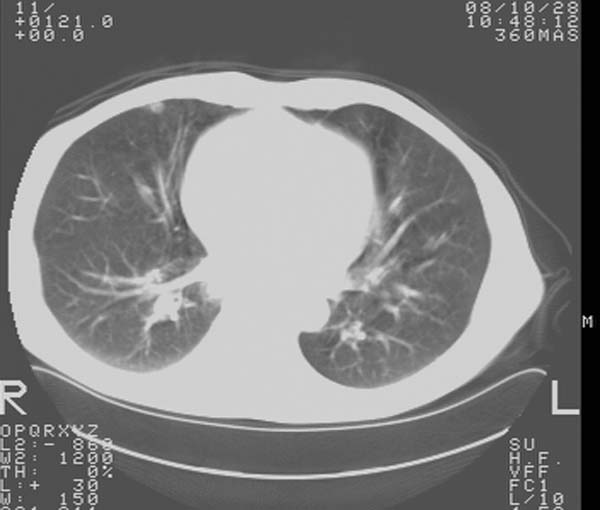

m,65y。半年前发现颈小结节,逐渐增多增大,现双侧耳后、颌下及颈部表浅淋巴肿大。胸片示双肺门增大。外院曾穿刺诊断为淋巴结核。在我科作胸腹部ct,我们觉得外院病检有误。现将图像上传请战友讨论。

纵隔内及腹膜后广泛淋巴结肿大,脾大,肝内似可见低密度影,结合病史半年前发现颈小结节,逐渐增多增大,现双侧耳后、颌下及颈部表浅淋巴肿大。考虑淋巴瘤。

纵隔,双肺门腹膜后多发淋巴结重大,非融合,肝脾轻度肿大,双肺野弥漫性小结节;考虑淋巴瘤,结节病可能性

纵隔内,双肺门、腋窝及腹膜后多发肿大淋巴结影,肺内小结节影,肝脾体积增大,支持淋巴瘤。肝内多发低密度影,考虑小囊肿。